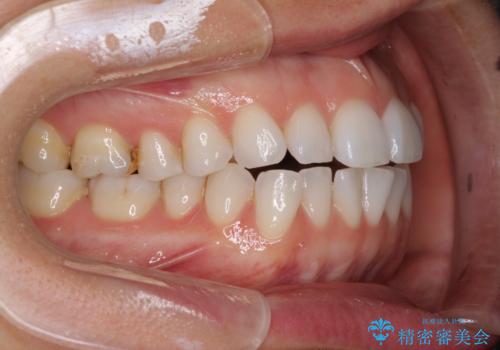

ちょっとしたデコボコをしっかりと改善したい インビザライン矯正

- 前歯のデコボコと上下スペースと前歯の隙間を気にして来院された患者様です。

目立たない装置を希望とのことでインビザラインにより、デコボコを解消しつつ、上下の前歯の隙間を閉じていくこととしました。

デコボコはあっという間に解消されましたが、上下前歯の隙間がなかなか解消されませんでした。

飲み込みの際に舌を前方に突出する癖があり、飲み込みの度に前歯に強く接触していたため、上下前歯の隙間が維持されていました。

舌の訓練を徹底していただいたことで、徐々に隙間は解消され、きれいな歯列に整えることができました。